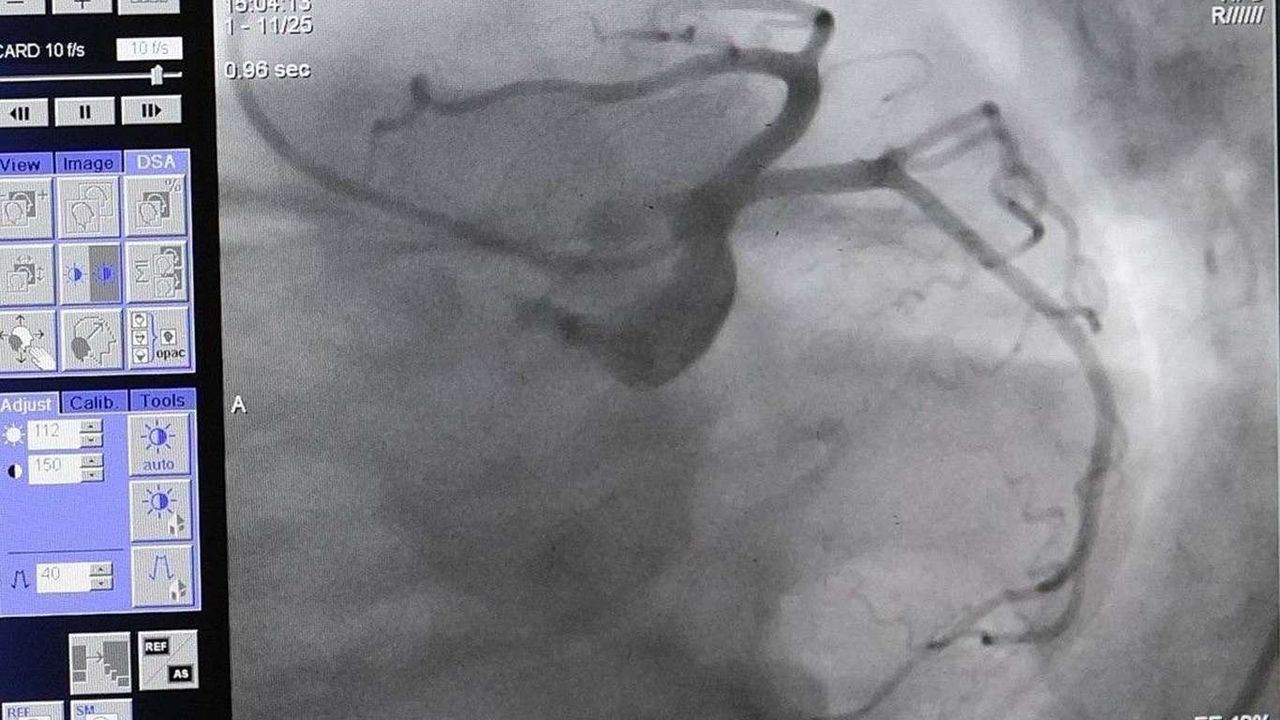

Dünyada en fazla ölümlerin yaşandığı hastalığın kap ve damar hastalıkları olduğuna dikkat çeken Kardiyoloji Uzmanı Dr. Gürkan İmre; sağlıklı beslenme, hareketli yaşam ve sigaradan uzak durmanın kalp sağlığını koruduğunu söyledi.